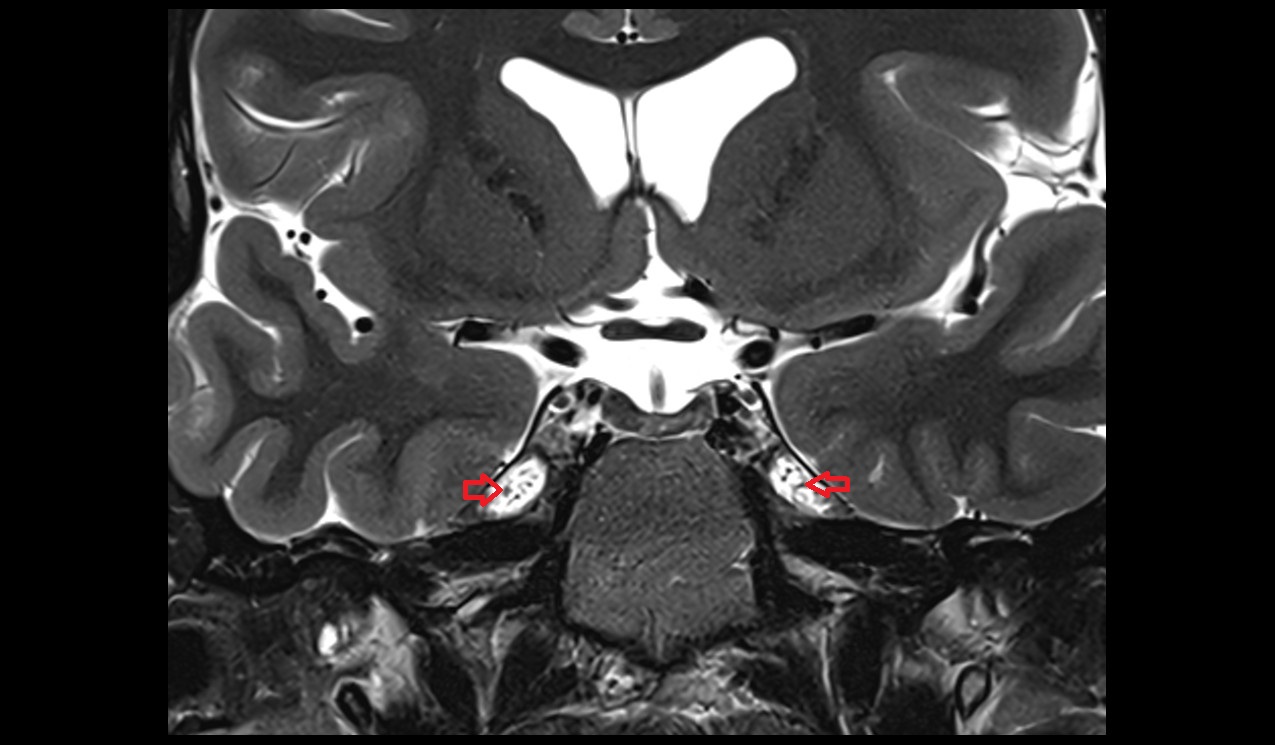

- Median aperture of fourth ventricle (foramen of Magendie)